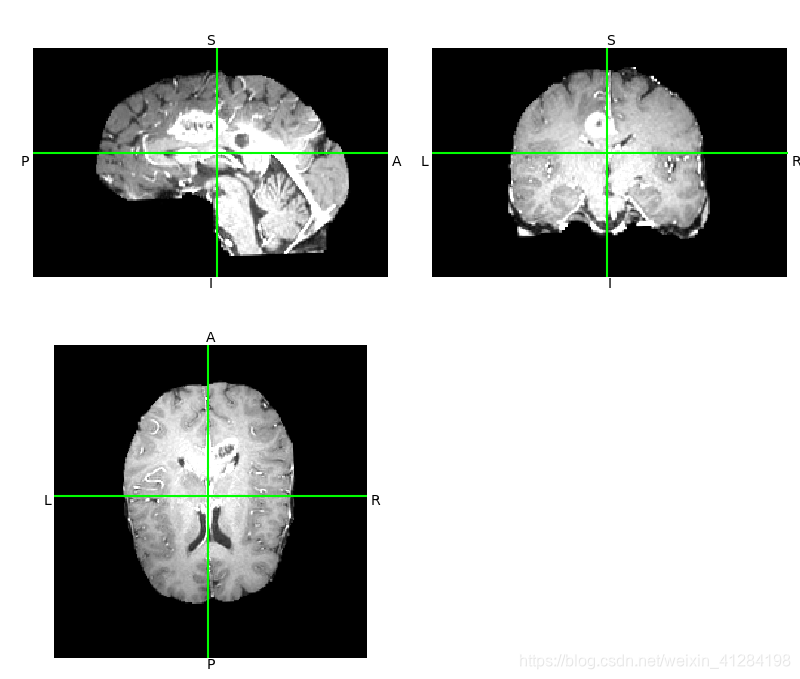

数据集:Brats2019数据集

import nibabel as nib

from nibabel.viewers import OrthoSlicer3D

example_filename = r'\HGG\BraTS19_2013_2_1\BraTS19_2013_2_1_t1ce.nii.gz'

img = nib.load(example_filename)

OrthoSlicer3D(img.dataobj).show()